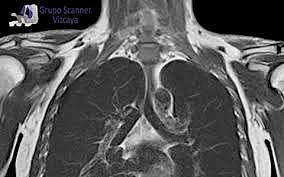

• Imagen del torax

Imagen del torax

En 1977, W. Hinshaw . publicaron imágenes de RM de la muñeca, R. Damadian logró reconstruir la imagen del tórax y P.